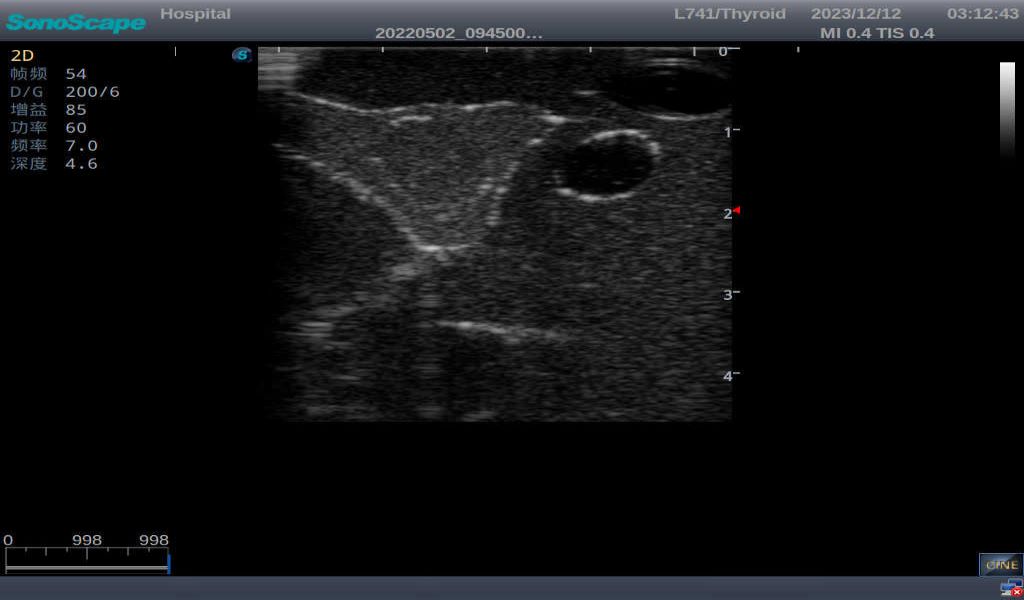

3)       It comes with four (4) thyroid modules and can show five (5) ultrasonic images: normal thyroid, thyroid adenoma, thyroid cancer, nodular goiter, thyroid cyst

Thyroid cyst, which fluid area, dark and echo-free area can be seen